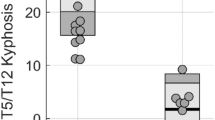

The surgery group consistently exhibited lower estimated mean elasticity compared to the brace group across all time points (Fig. 1). Significant differences in paraspinal muscle elasticity were observed between the two groups at baseline on the convex side (15.8 vs. 22.8 kPa, p = 0.037) and at 6 months on both the concave (12.1 vs. 22.7 kPa, p = 0.004) and convex (13.4 vs. 23.8 kPa, p = 0.005) sides (Table 1). However, there was no significant difference between the groups at 12 months.

Changes in the estimated mean elasticity values of the paraspinal muscles in the surgery and brace groups. The graph shows the estimated mean elasticity values of the paraspinal muscles at each time point. The surgery group shows lower muscle elasticity values at all time points than the brace group. The difference was statistically significant at baseline on the convex side (15.8 vs. 22.8 kPa, p = 0.037*) and at 6 months on both the convex (13.4 vs. 23.8 kPa, p = 0.005**) and concave (12.1 vs. 22.7 kPa, p = 0.004***) sides. There was a significant stiffness decrease from baseline to 6 months on the concave side in the surgery group (5.9 kPa, p = 0.025). There were no significant differences in elasticity between baseline and 12 months in both groups.

Comparison of elasticity change over time in paraspinal muscles between the surgery and brace groups

When considering the temporal change of paraspinal muscle elasticity in each group, both groups demonstrated temporal changes in elasticity (Fig. 1). In the surgery group, elasticity decreased at 6 months and recovered at 12 months. During 12 months, elasticity decreased significantly on the concave side from baseline to 6 months in the surgery group (estimated mean elasticity change 5.9 kPa [95% CI 0.7–11.0], p = 0.025) (Table 2). However, in the brace group, there were no significant changes in elasticity for 12 months. The paraspinal muscle elasticity was not significantly different between baseline and 12 months after treatment in both groups (Table 2). Furthermore, no asymmetry in elasticity was observed between the concave and convex sides of the paraspinal muscles during the study period (Table 3).